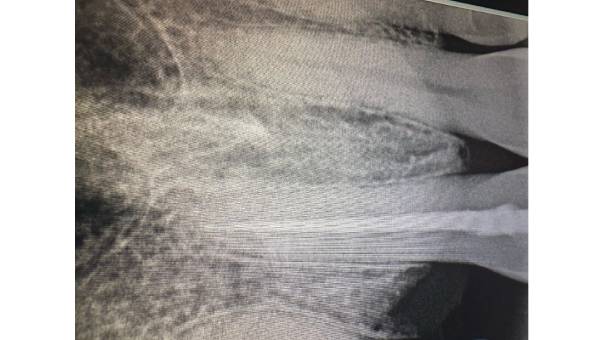

Mesioden In the IOPAR

Diagnosis: Upon clinical and radiographic examination, we discovered the presence of a mesioden—an extra tooth located between her Upper Right Central and Lateral Incisor. This supernumerary tooth was contributing to the spacing and misalignment in the anterior region.

Radiograph after extraction of the mesioden